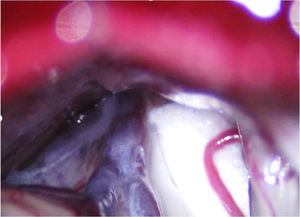

En la NT clásica se ha propuesto la siguiente clasificación del conflicto neurovascular (fig. 5): grado1, contacto simple; grado2, distorsión sin indentación, y grado3, indentación del vaso en el nervio73. Solo los tipos 2 y 3 se pueden considerar auténticas compresiones (fig. 6). La DCMV, propuesta por Gardner y desarrollada por Jannetta, consiste en la realización, bajo anestesia general, de una craneotomía de la fosa posterior de 2-3cm accediendo a la cisterna cerebelopontina mediante abordaje retromastoideo. Utilizando un microscopio quirúrgico se identifican los pares craneales y se puede utilizar la estimulación neurofisiológica para identificar el nervio facial. Una vez localizado el conflicto neurovascular, se procede con microdisectores a desplazar la estructura vascular para transposicionarla y separarla del nervio. Para evitar de nuevo el contacto y mantener ausencia o amortiguación del latido arterial, se colocan fragmentos microquirúrgicos de teflón (fig. 7) y se instila fibrina para evitar su desplazamiento. La tasa general de complicaciones de la DCMV es del 10 al 23%, pero diferentes estudios mostraron que son excepcionales en centros experimentados en cirugía de la NT74,75. La tabla 14 recoge los datos de eficacia y seguridad de la algunas de las técnicas quirúrgicas más empleadas en NT7,41,74-76.